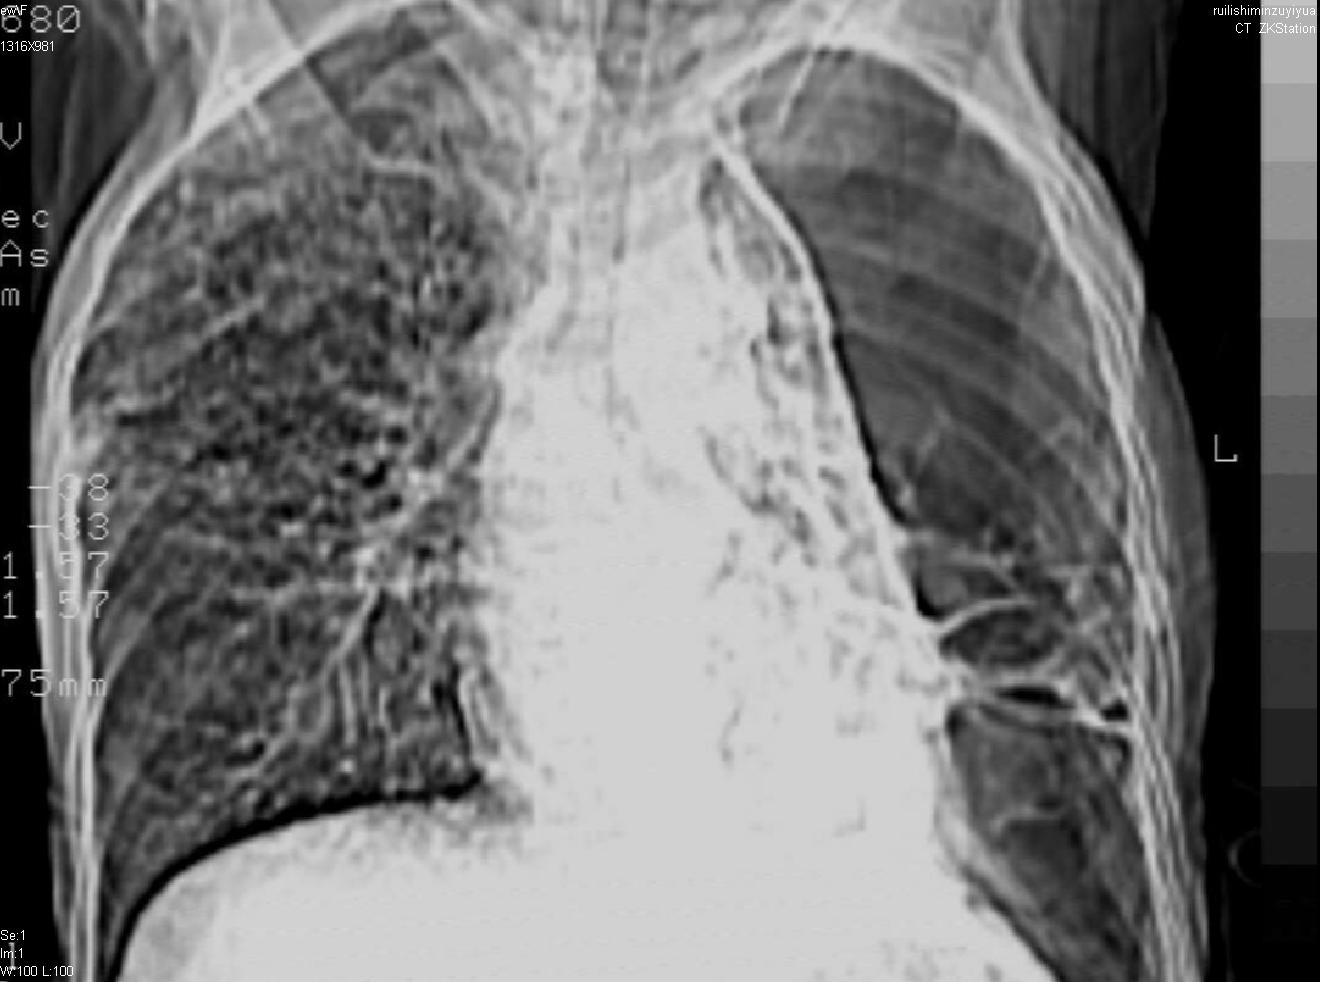

以下是引用天南地北在2007-6-11 23:32:00的发言:[br]1:左侧肺毁损(结核性)伴感染(多发空洞伴液平面)。[br]2:右肺继发型肺结核。

以下是引用avril在2007-6-12 1:17:00的发言:[br]1、左肺毁损。[br]2、左肺多发肺大泡伴自发性气液胸形成。[br]3、右肺继发型结核。